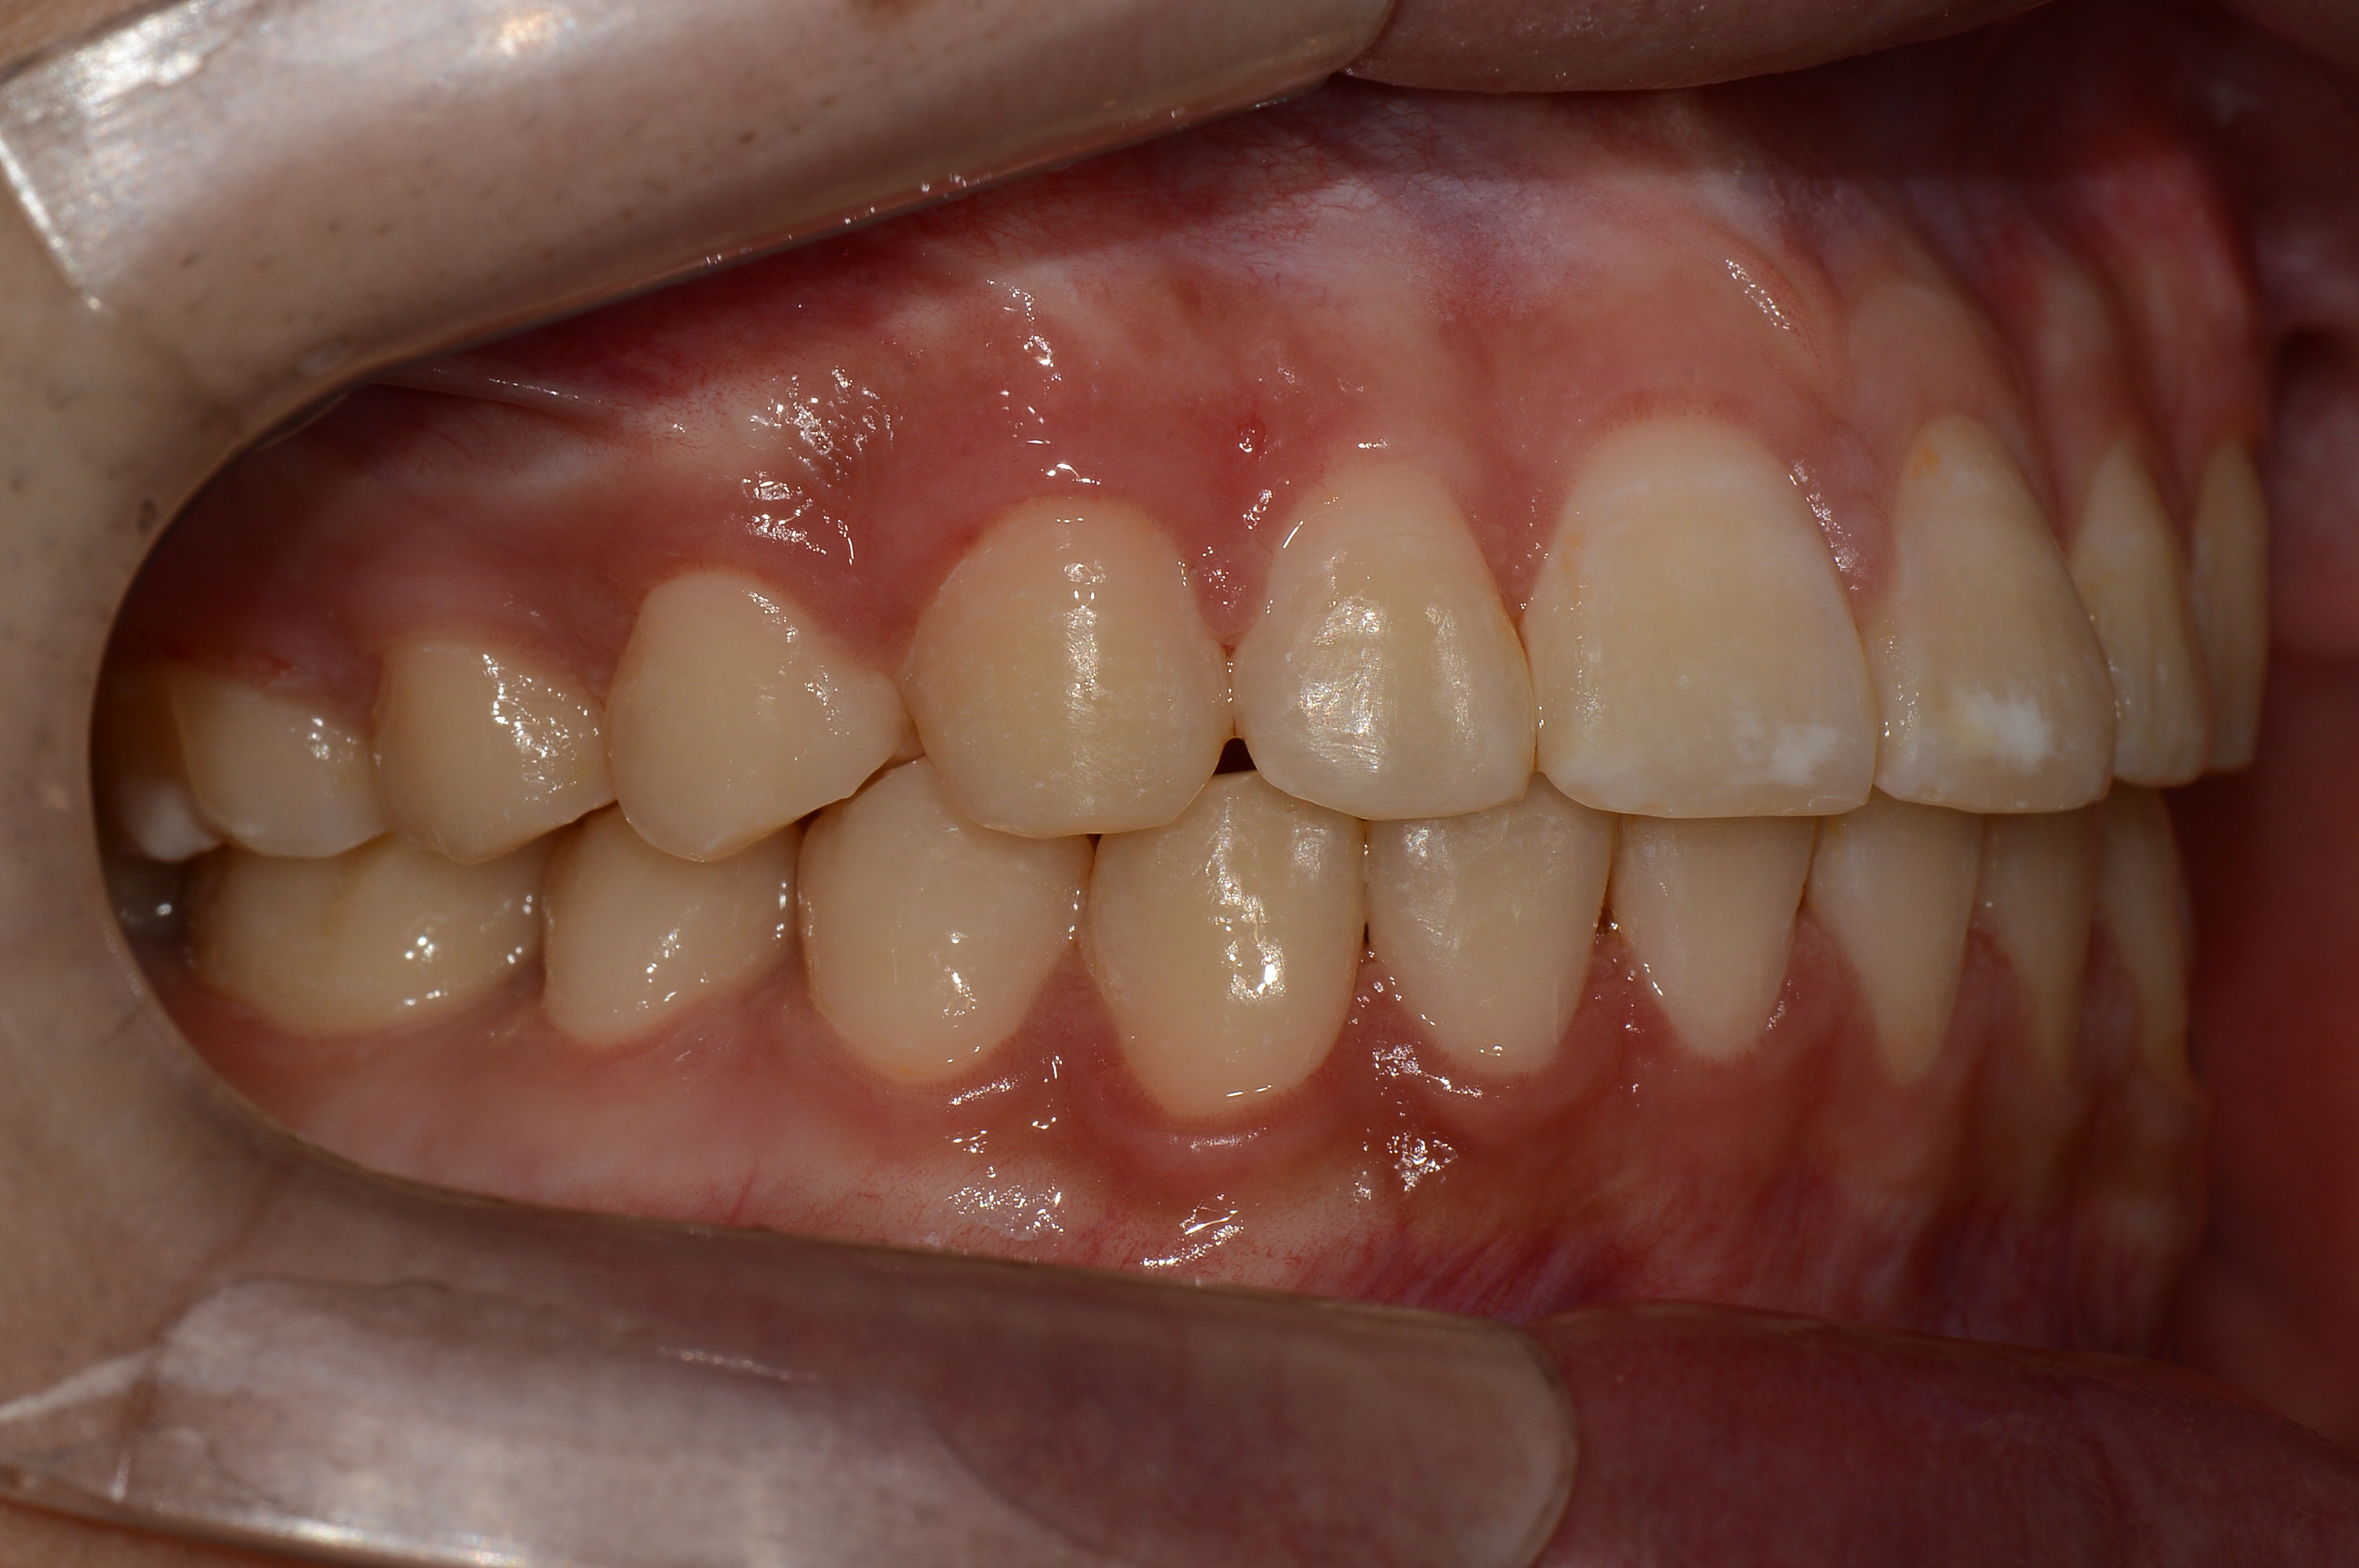

치료 후 사진입니다.